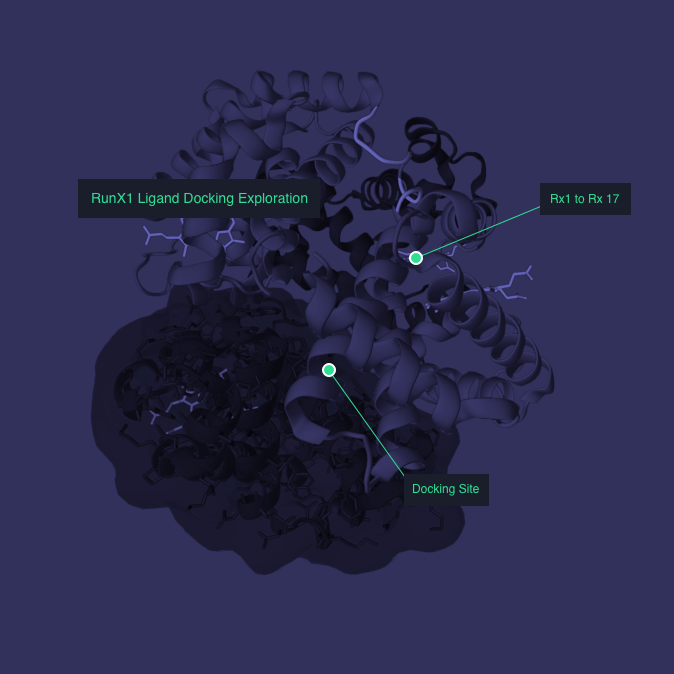

Application

Outcome

Autodesk Molecule Viewer created a new standard in molecular visualization. The application was featured in Nature Magazine and the London Museum of Design.